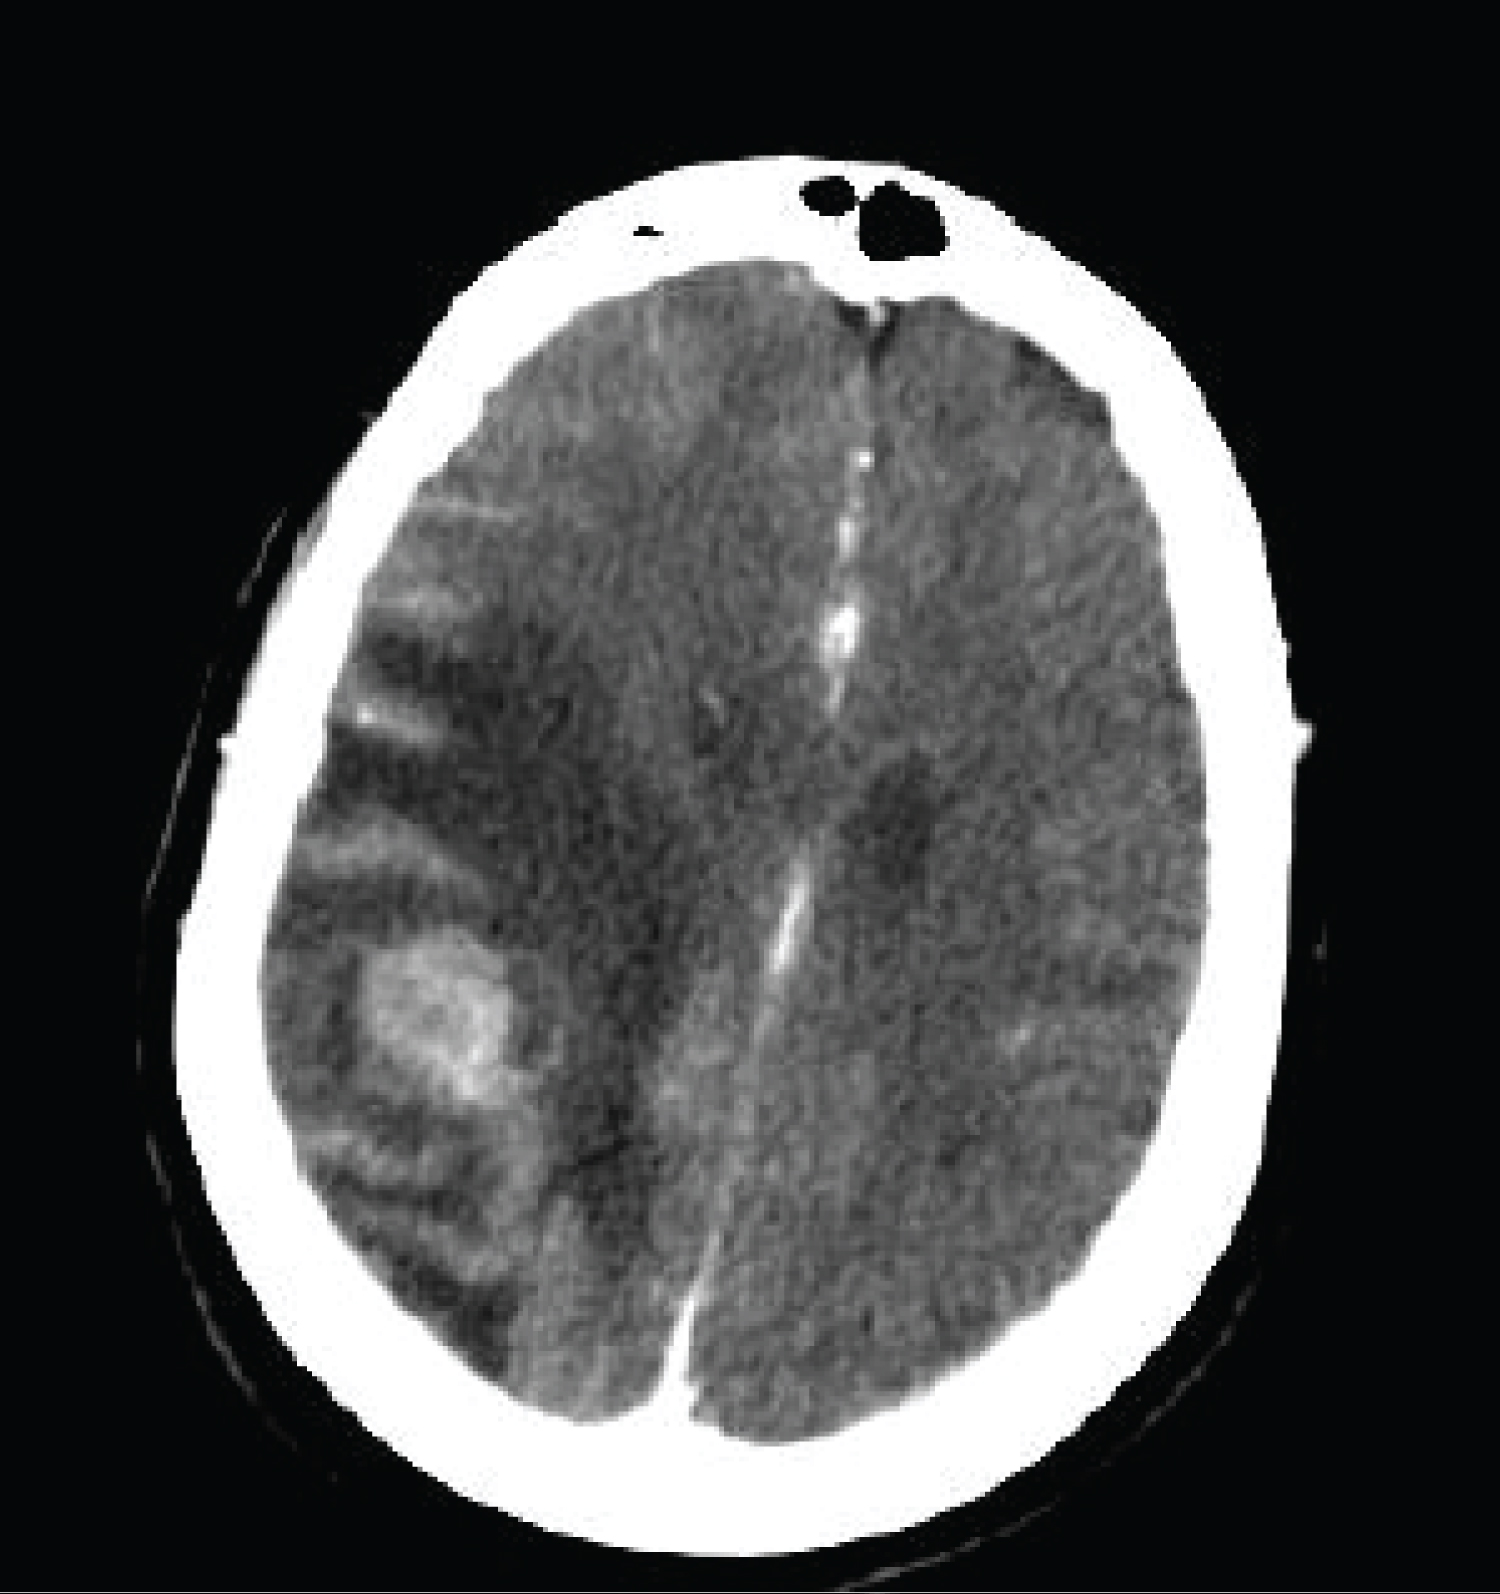

First patient: 66-years-old woman admitted to Adana City Education and Research Hospital or follow up after primary ovarian malignancy. She had the history of 3 years of primary ovarian malignancy (Stage III serous carcinoma) when admitted to our hospital. The patient was disease free for six years in routine follow up prosedure. After 9 years from diagnosis the patient was analyzed for abdominal discomfort. Abdominal tomography was revealed wall thickness on right ascending and transverse colon colonoscopy was performed. There was mass which wrap the whole wall of distal of ascending colon. Colonoscopic biopsy was reported ovarian serous carcinoma metastasis to the colon. Neoplastic infiltration was reported from submucosa to the muscularis propria. Immunohistochemistry was revealed as not primary colon carcinoma it was reported as metastasis from primary ovarian carcinoma. PET/CT staging showed infraclavicular, mediastinal, paratrakeal, precarinal, left hilar parasternal multiple lymph nodes, right transverse colon wall thickness, retroperitoneal, paraaortic multiple lymph nodes. Ca 125 level was 36 IU/ml. The biopsy was performed from one of the peripheral lymph nodes. The pathology was reported as the metastasis of ovarian carcinoma. Platine sensitive recurrence was treated with taxane/platinum combination. Complete response was detected on PET scan. The patient was followed by routine follow up. Cranial CT and MRI was performed after 7.5 months from the last therapy due to headache. One cranial mass on right deep pariatel lobe was detected (Figure 1). On PET-CT scan; there was only right paratracheal suspicious reactive? milimetric lymph node. No other extracranial metastases were observed at the PET scan. Ca125 level was 15.3 IU/ml. Cranial metastesectomy was performed. Pathology was reported as cranial serous ovarian carcinoma metastasis. In immunohistochemistry CK7(+), WT1(+), CD56(+), P16(+) ER(+), Vimentin(-) CEA(-) P53(-). A post-surgery Stereotactic radiosurgery (SRS) to the surgical cavity has been performed followed by a systemic chemotherapy by carboplatin + taxane for six cycles. Platine + taxane treatment was administered to the patient due to platine sensitive recurrence. Bevacizumab should not be given with this combination without permission due to social security reasons in Turkey Government. Carboplatine and paclitaxel combination with or without bevacizumab is acceptable combination in platine sensitive recurrence due to National Comprehensive Cancer Network (NCCN) Guidelines. After three cycles of therapy there was no evidence of disease on both PET and MRI. After 6 months after treatment the patient died due to cardiac reason. Patient had approximately 11 year history of ovarian cancer. After 9 years firstly lymph nodes and colonic metastasis and then brain metastasis treated successfully.

Figure 1: Right parietal mass in CT. View Figure 1